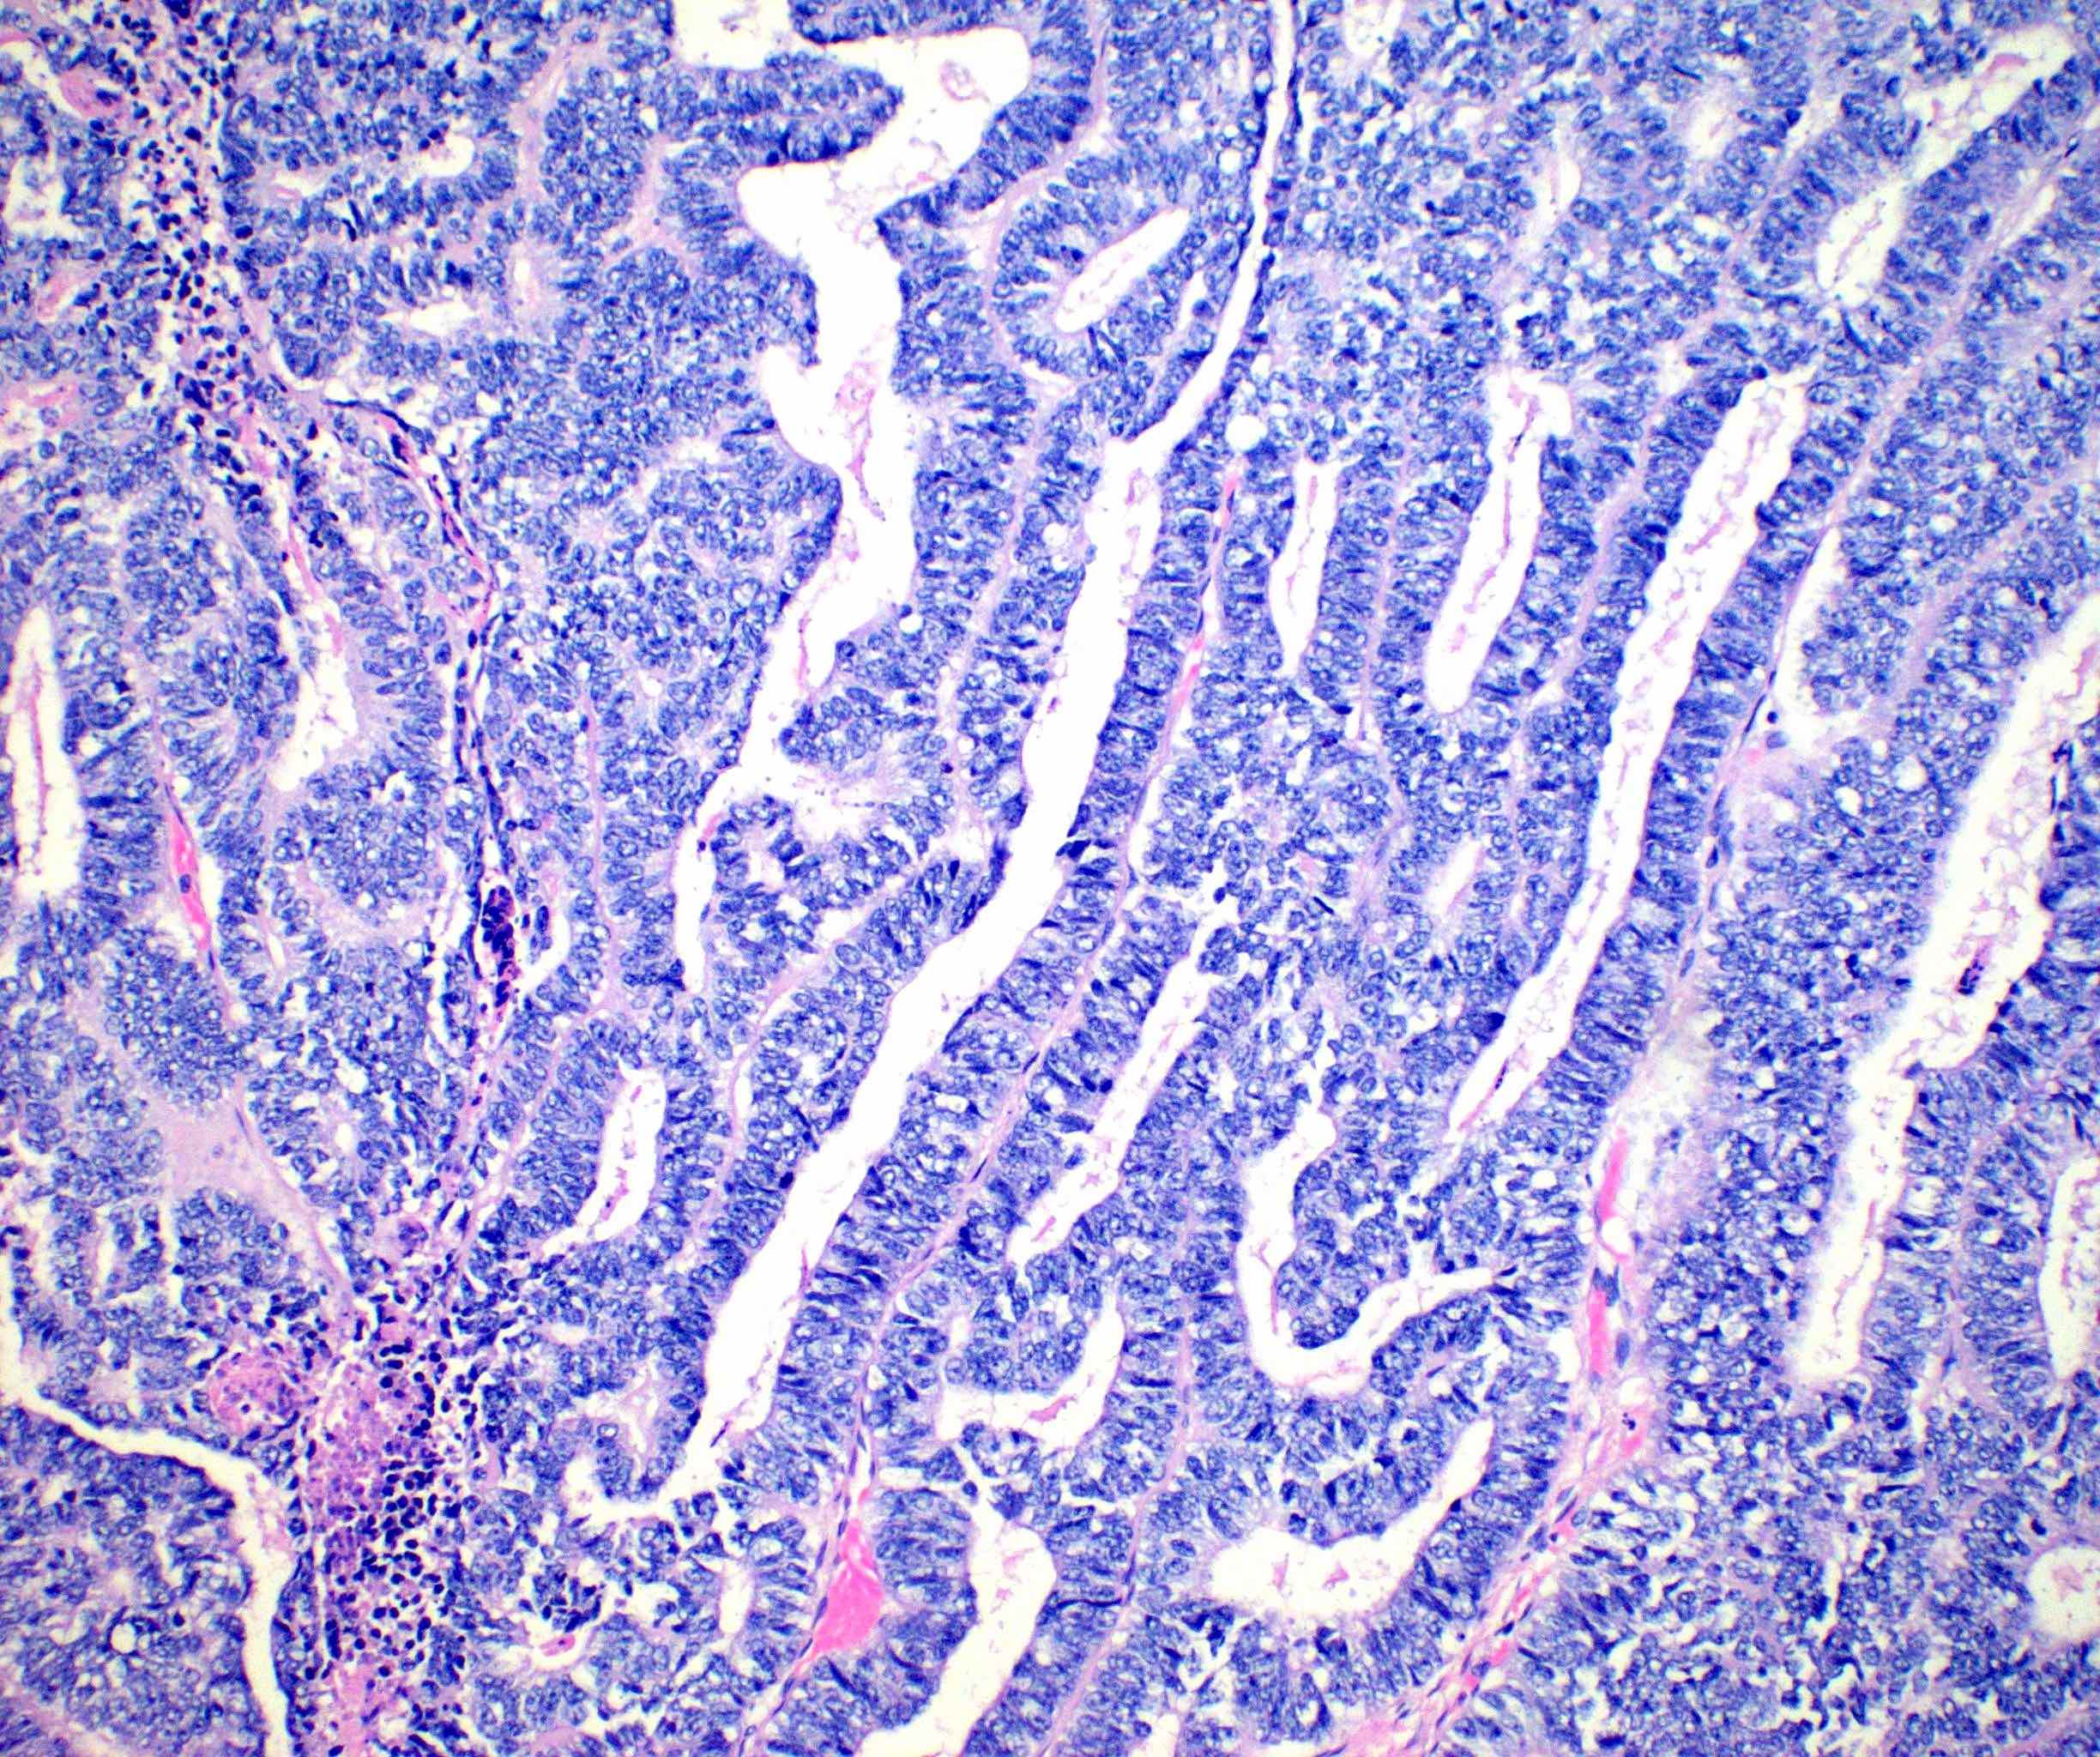

- Variety of histologic patterns that may be present within the same tumor

- Most frequently small tubules with ductal / glandular growth

- Papillary, solid growth, trabecular, retiform, sex cord-like, sieve-like, glomeruloid and spindle cell areas have all been described

- Luminal eosinophilic secretions are characteristic but not always identified

- Tumor cells can be flattened, cuboidal or columnar with mild to moderate cytological atypia

- Clear cell features can be seen but are less common

- High grade cytological atypia is usually not a predominant feature

- Nuclei show vesicular chromatin and nuclear grooves

- Sarcomatoid transformation has been seen in rare instances

- Squamous, ciliated or mucinous differentiation (metaplasia) are not present and there are no associated mesonephric remnants (J Clin Med 2021;10:698)

Microscopic (histologic) images

Contributed by Daniel Graham, M.D., Adele Wong, M.B., B.Ch., B.A.O. and Lucy Ma, M.D.